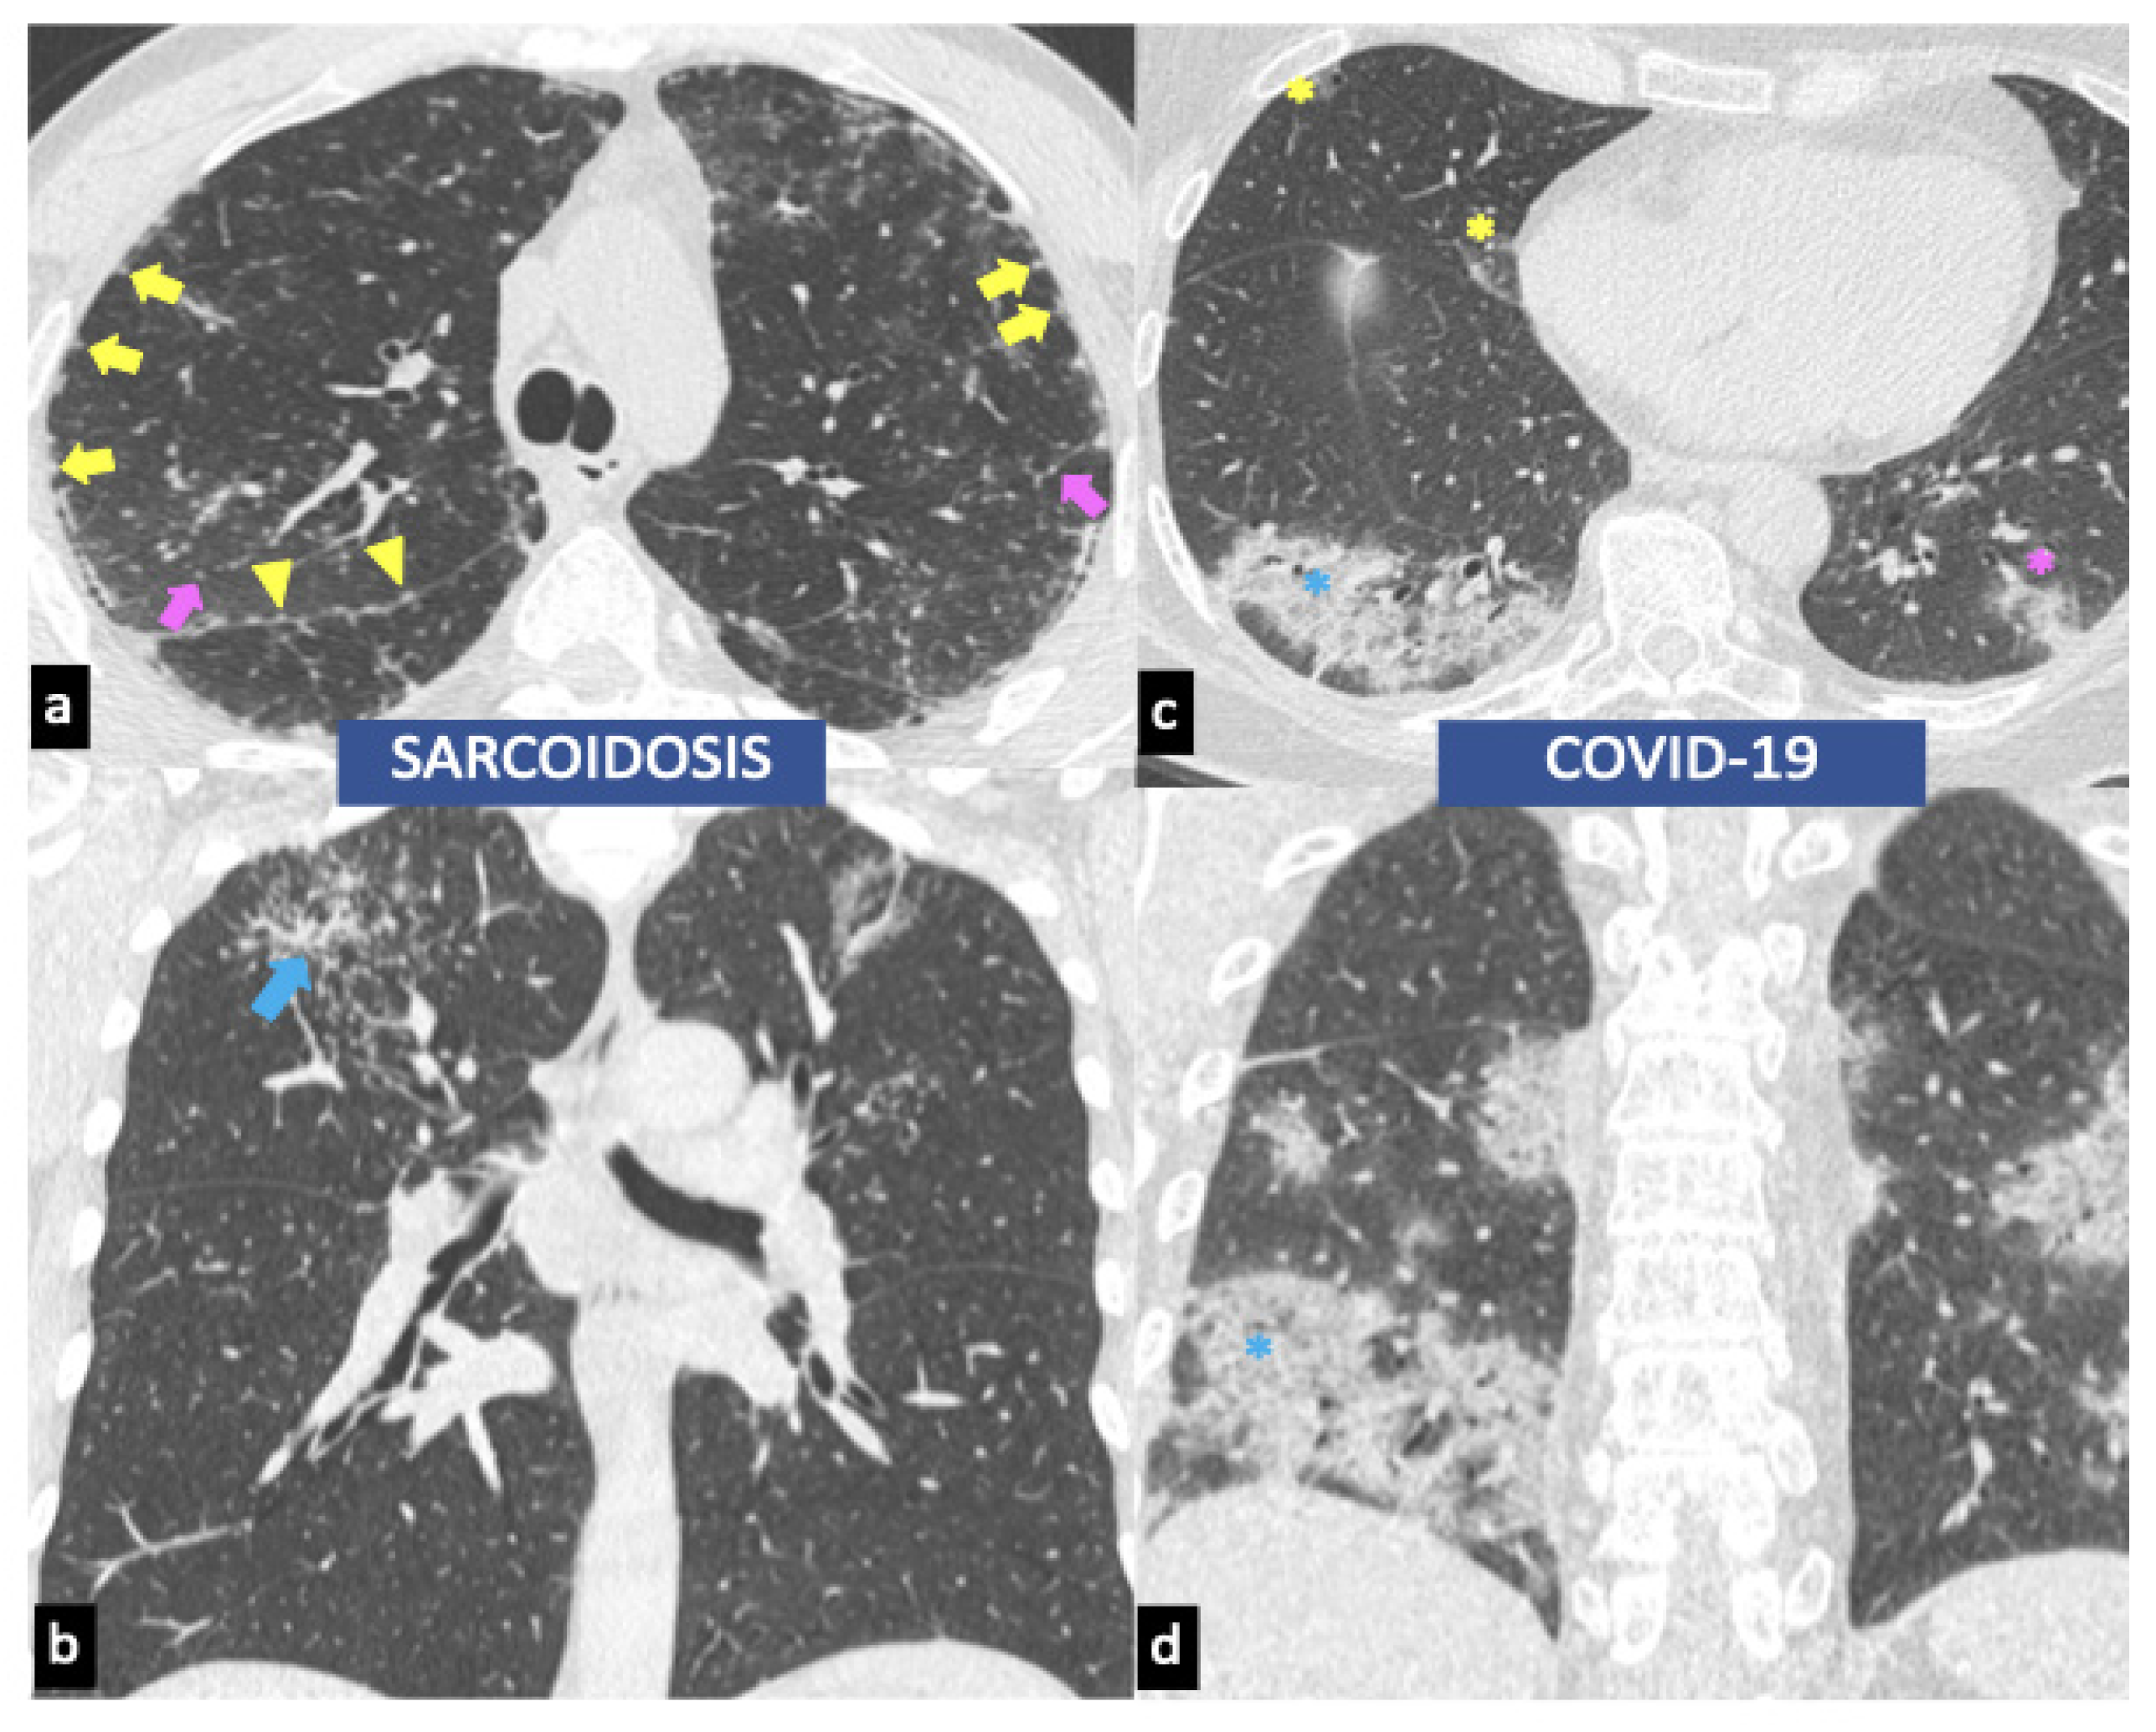

Sarcoidosislike reaction. A&B. Contrastenhanced axial chest CT images Sarcoidosis Protein Gap Sarcoidosis, a systemic granulomatous disease of unknown etiology, may mimic other conditions at presentation often resulting in delayed. Serum protein electrophoresis is an. Immunoglobulin deficiency syndromes in sarcoidosis are infrequent and are discovered only when sarcoidosis patients develop recurrent. A polyclonal increase in immunoglobulins. Sarcoidosis is a systemic granulomatous disease which carries variable outcomes. In view of the fact that. Sarcoidosis Protein Gap.

JCM Free FullText Imaging of Pulmonary Sarcoidosis—A Review Sarcoidosis Protein Gap In this review we highlight various investigations used to diagnose sarcoidosis, outline proposed biomarkers, and discuss novel methods of sampling biomarkers. Diagnosis of sarcoidosis relies on three criteria: Serum protein electrophoresis is an. Sarcoidosis risk varies by age, sex, race, and ethnic background, leading to widely varying worldwide incidence and prevalence. (1) a compatible clinical and radiologic presentation, (2) pathologic. Sarcoidosis Protein Gap.

Biomedicines Free FullText Sarcoidosis and COVID19 At the Cross Sarcoidosis Protein Gap Sarcoidosis risk varies by age, sex, race, and ethnic background, leading to widely varying worldwide incidence and prevalence. Diagnosis of sarcoidosis relies on three criteria: In view of the fact that current biomarker profiles in sarcoidosis are scarce, fragmented and mostly not validated, there is. Serum protein electrophoresis is an. (1) a compatible clinical and radiologic presentation, (2) pathologic evidence. Sarcoidosis Protein Gap.

Biomedicines Free FullText Sarcoidosis and COVID19 At the Cross Sarcoidosis Protein Gap A polyclonal increase in immunoglobulins. (1) a compatible clinical and radiologic presentation, (2) pathologic evidence of noncaseating granulomas, and (3) exclusion. Serum protein electrophoresis is an. Immunoglobulin deficiency syndromes in sarcoidosis are infrequent and are discovered only when sarcoidosis patients develop recurrent. Sarcoidosis risk varies by age, sex, race, and ethnic background, leading to widely varying worldwide incidence and prevalence.. Sarcoidosis Protein Gap.